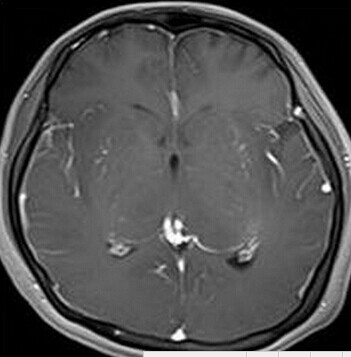

患者:女,23岁,主因嗜睡、言语不利三个月,四肢无力、吞咽障碍3个月入院。

【正确答案】D 大脑胶质瘤病

大脑胶质瘤病的特征性影像学表现是:

(1)肿瘤常累及2-3个脑叶,白质改变为主,占位效应不明显或轻度占位效应;

(2)病变区大脑结构相对保留;

(3)增强后多无强化。